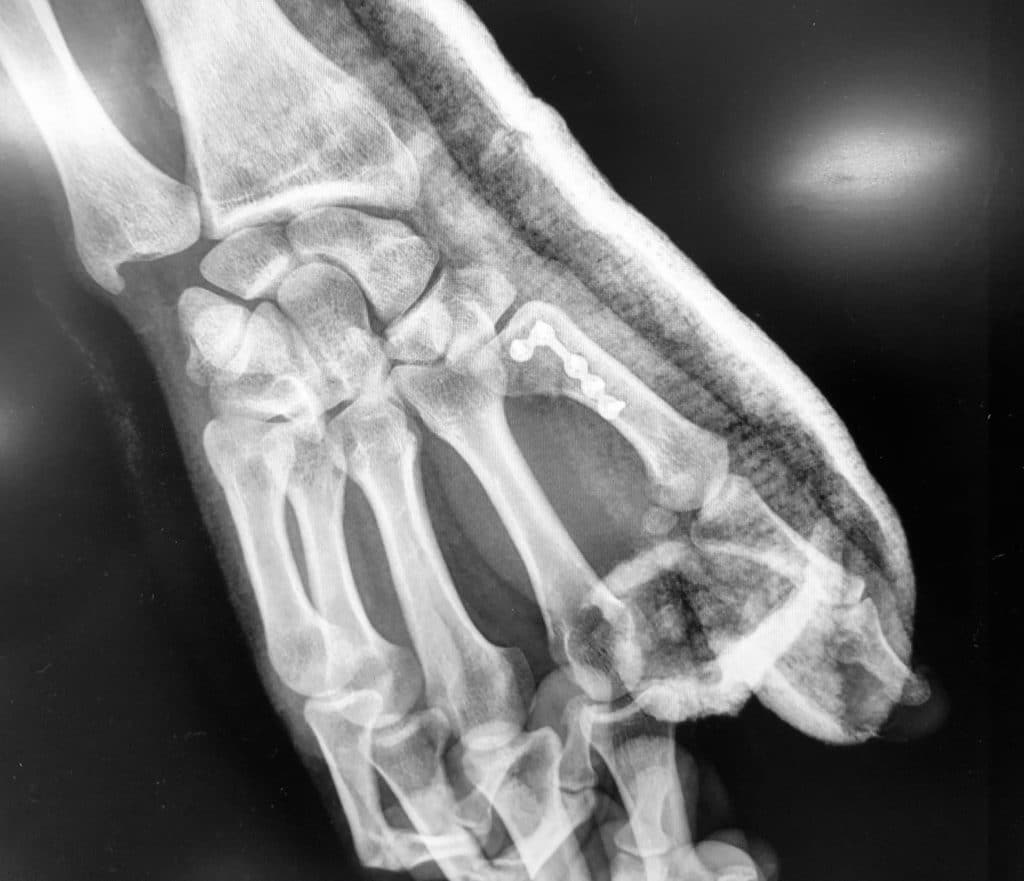

Les fractures ouvertes, ou déplacées avec troubles de rotation seront traitées chirurgicalement. Le choix du traitement chirurgical est fonction de l’os atteint, du siège et du type de fracture.

Schématiquement, la stabilisation après réduction de la fracture est faite soit par broche soit par plaque. Cette chirurgie réalisée en ambulatoire sous anesthésie du bras, doit permettre une rééducation précoce afin de restaurer la fonction de la main. Des pansements sont à faire réaliser par infirmière durant deux à trois semaines. La rééducation sera donc précoce afin de limiter la raideur.

Plaque P1

Différentes plaques des os de la main